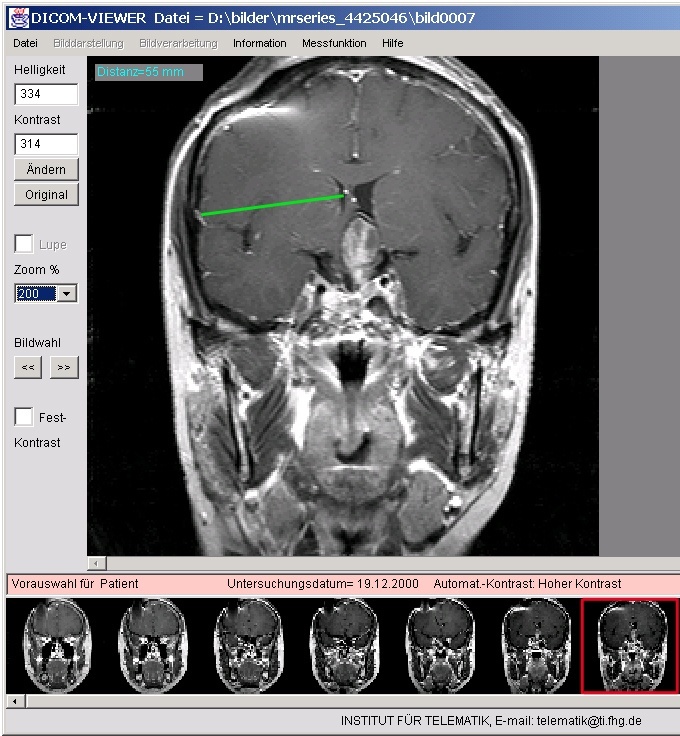

Einen Ausweg bietet das »Patienten-CD-System«, das am Institut für Telematik in Trier entwickelt wurde. »Unsere Zusammenarbeit mit mehreren Krankenhäusern in Trier brachte uns auf die Idee, ein besonders benutzerfreundliches und vollautomatisiertes System für das Archivieren von medizinischen Bildern aller Art auf CompactDisk zu entwickeln«, erinnert sich Professor Christoph Meinel, Leiter des von der Fraunhofer-Gesellschaft betreuten Instituts. »Besondere Vorkenntnisse, um die CDs zu brennen oder die Bilder zu betrachten, sind nun nicht mehr nötig.«

Das Schreibmodul ist eine Komponente des Systems. Es dient dazu, die medizinischen Bilder von Aufnahmegeräten oder Workstations zu sammeln, zu visualisieren und über einen CD-Brenner zu archivieren. DICOM ist dabei das unter Medizinern anerkannte und international gebräuchliche Dateiformat. Das zweite Modul ist der Viewer. Er stellt alle nötigen Werkzeuge zur Verfügung, um ein Bild oder Sequenzen mit hoher Auflösung darstellen und bearbeiten zu können. Der Viewer wird ebenfalls auf die CD gebrannt. Er ermöglicht es anderen Ärzten oder Therapeuten, die Aufnahmen ohne eigene Software auf ihrem PC betrachten zu können. Das gleiche gilt für den Patienten: Die bis zu 1 000 Bilder seines Innenlebens kann er mit einer CD nach Hause nehmen und dort das ungeborene Kind oder den Knochenbruch Freunden und Verwandten vorführen oder ausdrucken.